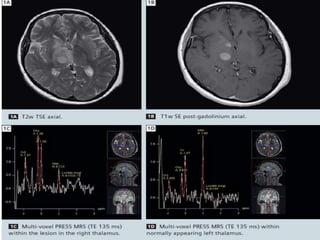

45-year-old woman presenting with

right hemiparesis and headache. A)

Axial T1-weighted image (TR 450, TE

20, NEX 1, 0.2 mmol/Kg gadolinium

injected at 5 cc/s) shows an

enhancing lesion in the right pons,

midbrain, and thalamus. B) CBV map

shows elevated blood volume within

the lesion, consistent with high-grade

neoplasm (perfusion raw data

obtained at TR 500, TE 65, 5-mm

thick, 6-mm skip, 0.2 mmol/Kg

gadolinium injected at 5 cc/s). C) MR

spectroscopy shows a high choline to

creatine ratio and a decrease in N-acetyl

aspartate, also consistent with

high-grade tumor (single voxel

technique, TR 1500, TE 144). D) FDG-PET

shows foci of high glucose

metabolism within the lesion, also

consistent with high-grade tumor.